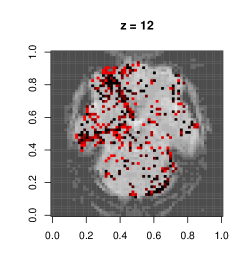

This dataset is due to Wakeman & Henson (2015), where each of the 19 subjects go through 9 runs of consecutive visual tasks. Blood oxygen level readings are recorded across time as 3D images made of (total 135,168) voxels. Here we use the data from a single run and task on subject 1, and aim to estimate dependence patterns of readings across 210 time points and areas of the brain.

We fit separate regressions at each voxel (Appendixย E), with second order autoregressive terms, neighboring voxel readings and one-hot encoded visual task categories in the design matrix. After applying the e-value feature selection, we compute the F-statistic at each voxel using selected coefficients only, and obtain their p-values. Fig.ย 7.1c highlights voxels with p-values . Left and right visual cortex areas show high spatial dependence, with more dependence on the left side. Signals from the right visual field obtained by both eyes are processed by the left visual cortex. The lop-sided dependence pattern suggests that visual signals from the right side led to a higher degree of processing in our subjectโs brain. We also see activity in the cerebellum, the role of which in visual perception is well-known (Calhoun etย al., 2010; Kirschen etย al., 2010).

Appendix E Details of fMRI data implementation

Typically, the brain is divided by a grid into three-dimensional array elements called voxels, and activity is measured at each voxel. More specifically, a series of three-dimensional images are obtained by measuring Blood Oxygen Level Dependent (BOLD) signals for a time interval as the subject performs several tasks at specific time points. A single fMRI image typically consists of voxels in the order of , which makes even fitting the simplest of statistical models computationally intensive when it is repeated for all voxels to generate inference, e.g. investigating the differential activation of brain region in response to a task.

The dataset we work with comes from a recent study involving 19 test subjects and two types of visual tasks (Wakeman & Henson, 2015). Each subject went through 9 runs, in which they were showed faces or scrambled faces at specific time points. In each run 210 images were recorded in 2 second intervals, and each 3D image was of the dimension of , which means there were 135,168 voxels. Here we use the data from a single run on subject 1, and perform a voxelwise analysis to find out the effect of time lags and BOLD responses at neighboring voxels on the BOLD response at a voxel. Formally we consider separate models at voxel , with observations across time points .

Clubbing together the stimuli, drift, neighbor and autoregressive terms into a combined design matrix and coefficient vector , we can write . We estimate the set of non-zero coefficients in using the e-value method. Suppose this set is , and its subsets containing coefficient corresponding to neighbor and non-neighbor (i.e. stimuli and drift) terms are and , respectively. To quantify the effect of neighbors we now calculate the corresponding -statistic:

and obtain its -value, i.e. .

Figureย E.1 shows plots of the voxels with a significant -value from the above -test, with a darker color associated with lower p-value, as opposed to the smoothed surface in the main paper. Most of the significant terms were due to the coefficients corresponding to neighboring terms. A very small proportion of voxels had any autoregressive effects selected (less than 1%), and most of them were in regions of the image that were outside the brain, indicating noise.